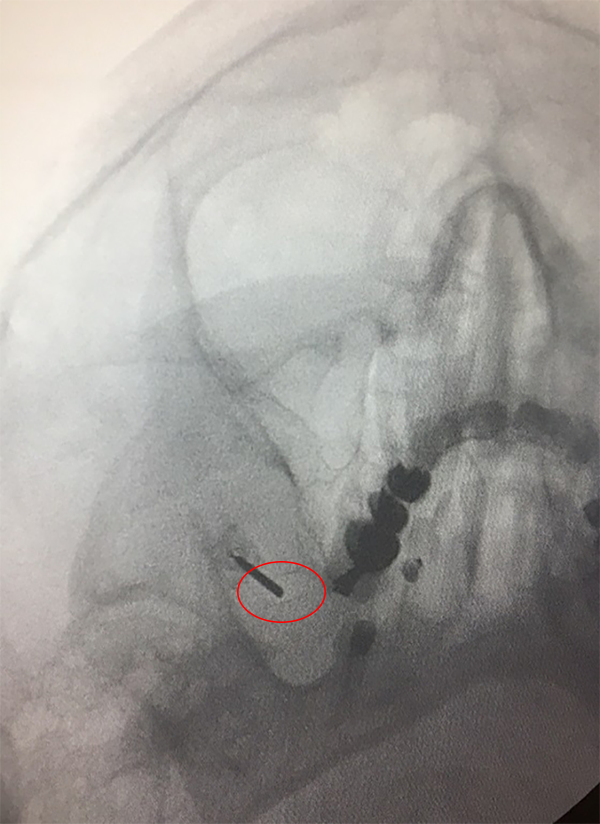

En todos los casos se colocó el paciente sobre la camilla de cirugía apoyando la cabeza sobre un cabezal radio lucido, se giró la cabeza levemente 20° aproximadamente hacia el lado opuesto a la neuralgia, allí se marcó luego los puntos de Hartel: un punto inmediatamente medial y debajo de la pupila, un punto a 3 cm delante del conducto auditivo externo para obtener la trayectoria rostral/caudal y medial/lateral respectivamente. El último punto se ubicó a 2.5 cm lateral a la comisura labial. Se realizó radioscopia para objetivar el foramen oval homolateral al dolor (fig. 1). Se procedió a realizar sedo analgesia en el paciente con propofol. Bajo radioscopia y previo campo estéril se realizó la punción, a 2.5 cm en sentido lateral a la comisura labial intentando introducir la cánula para termocoagulación por radiofrecuencia de 10 cm con punta recta de 5 mm por el foramen oval en su porción medial, una vez canulado el foramen y dentro de la cisterna trigeminal se objetivó la mayoría de las veces, no siempre, la salida de líquido céfalo raquídeo (LCR) (fig. 2). Se realizó radioscopia en sentido lateral tomando como referencia el piso de la silla turca y el clivus a 5 mm, 10 mm o 15 mm según cual rama se quiso estimular, rama V1, V2 o V3 respectivamente (fig. 3). Se conectó la aguja al electrodo de radiofrecuencia previamente conectado al dispositivo generador de radiofrecuencia (FL Fisher Neuro N50) (fig. 4), para estimular la rama motora a 5 Hz, una vez despierto el paciente se procedió a realizar estimulación a 50 Hz para objetivar el patrón de dolor habitual.

Figura 1: Identificación del Foramen Oval.

Figura 2: Introducción de la Cánula.